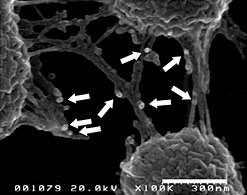

図6 Lypd8はプロテウス菌の鞭毛に結合する

プロテウス菌とLypd8蛋白質を反応後、蛋白質に対する抗体を用いてLypd8を標識し、走査型電子顕微鏡にて観察。Lypd8蛋白質とプロテウス菌鞭毛の結合が観察された。矢印で示した粒状の構造がLypd8蛋白質と鞭毛との結合を示している。